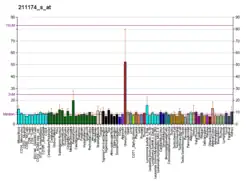

molecular complex of cholecystokinin-8 and n-terminus of the cholecystokinin a receptor by nmr spectroscopy | |||||||||